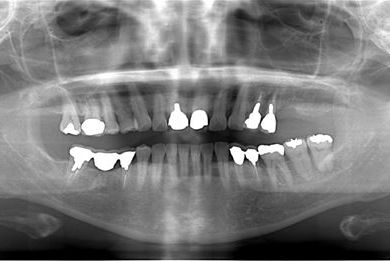

骨再生インプラント治療+セラミック治療+歯肉歯槽骨整形手術

| 治療方針 | ソケットリフトにより上顎洞を拳上し、骨再生法を行い、インプラント治療を可能にする。 | ||||||||||||||||||||||||||||||||

| 治療内容 | インプラント2本(ソケットリフト、GBR)、メタルボンドセラミッククラウン3本、歯肉歯槽骨整形手術 | ||||||||||||||||||||||||||||||||